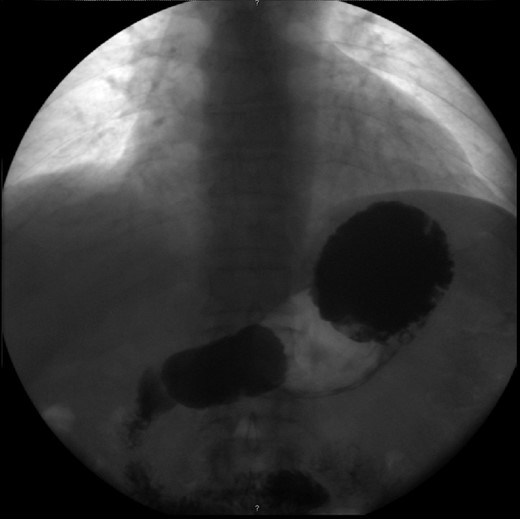

The patient was submitted to exploratory laparotomy, during which a mesenteroaxial GV was found, showing great laxity of the peritoneal ligaments and a bulky stomach (Fig. 3). The surgeons decided to perform a partial gastrectomy, from which the patient recovered uneventfully. She was discharged on the ninth post-operative day and presented no complaints 1 year after the surgery.

Findings during exploratory laparotomy, showing great laxity of the peritoneal ligaments and a bulky stomach.